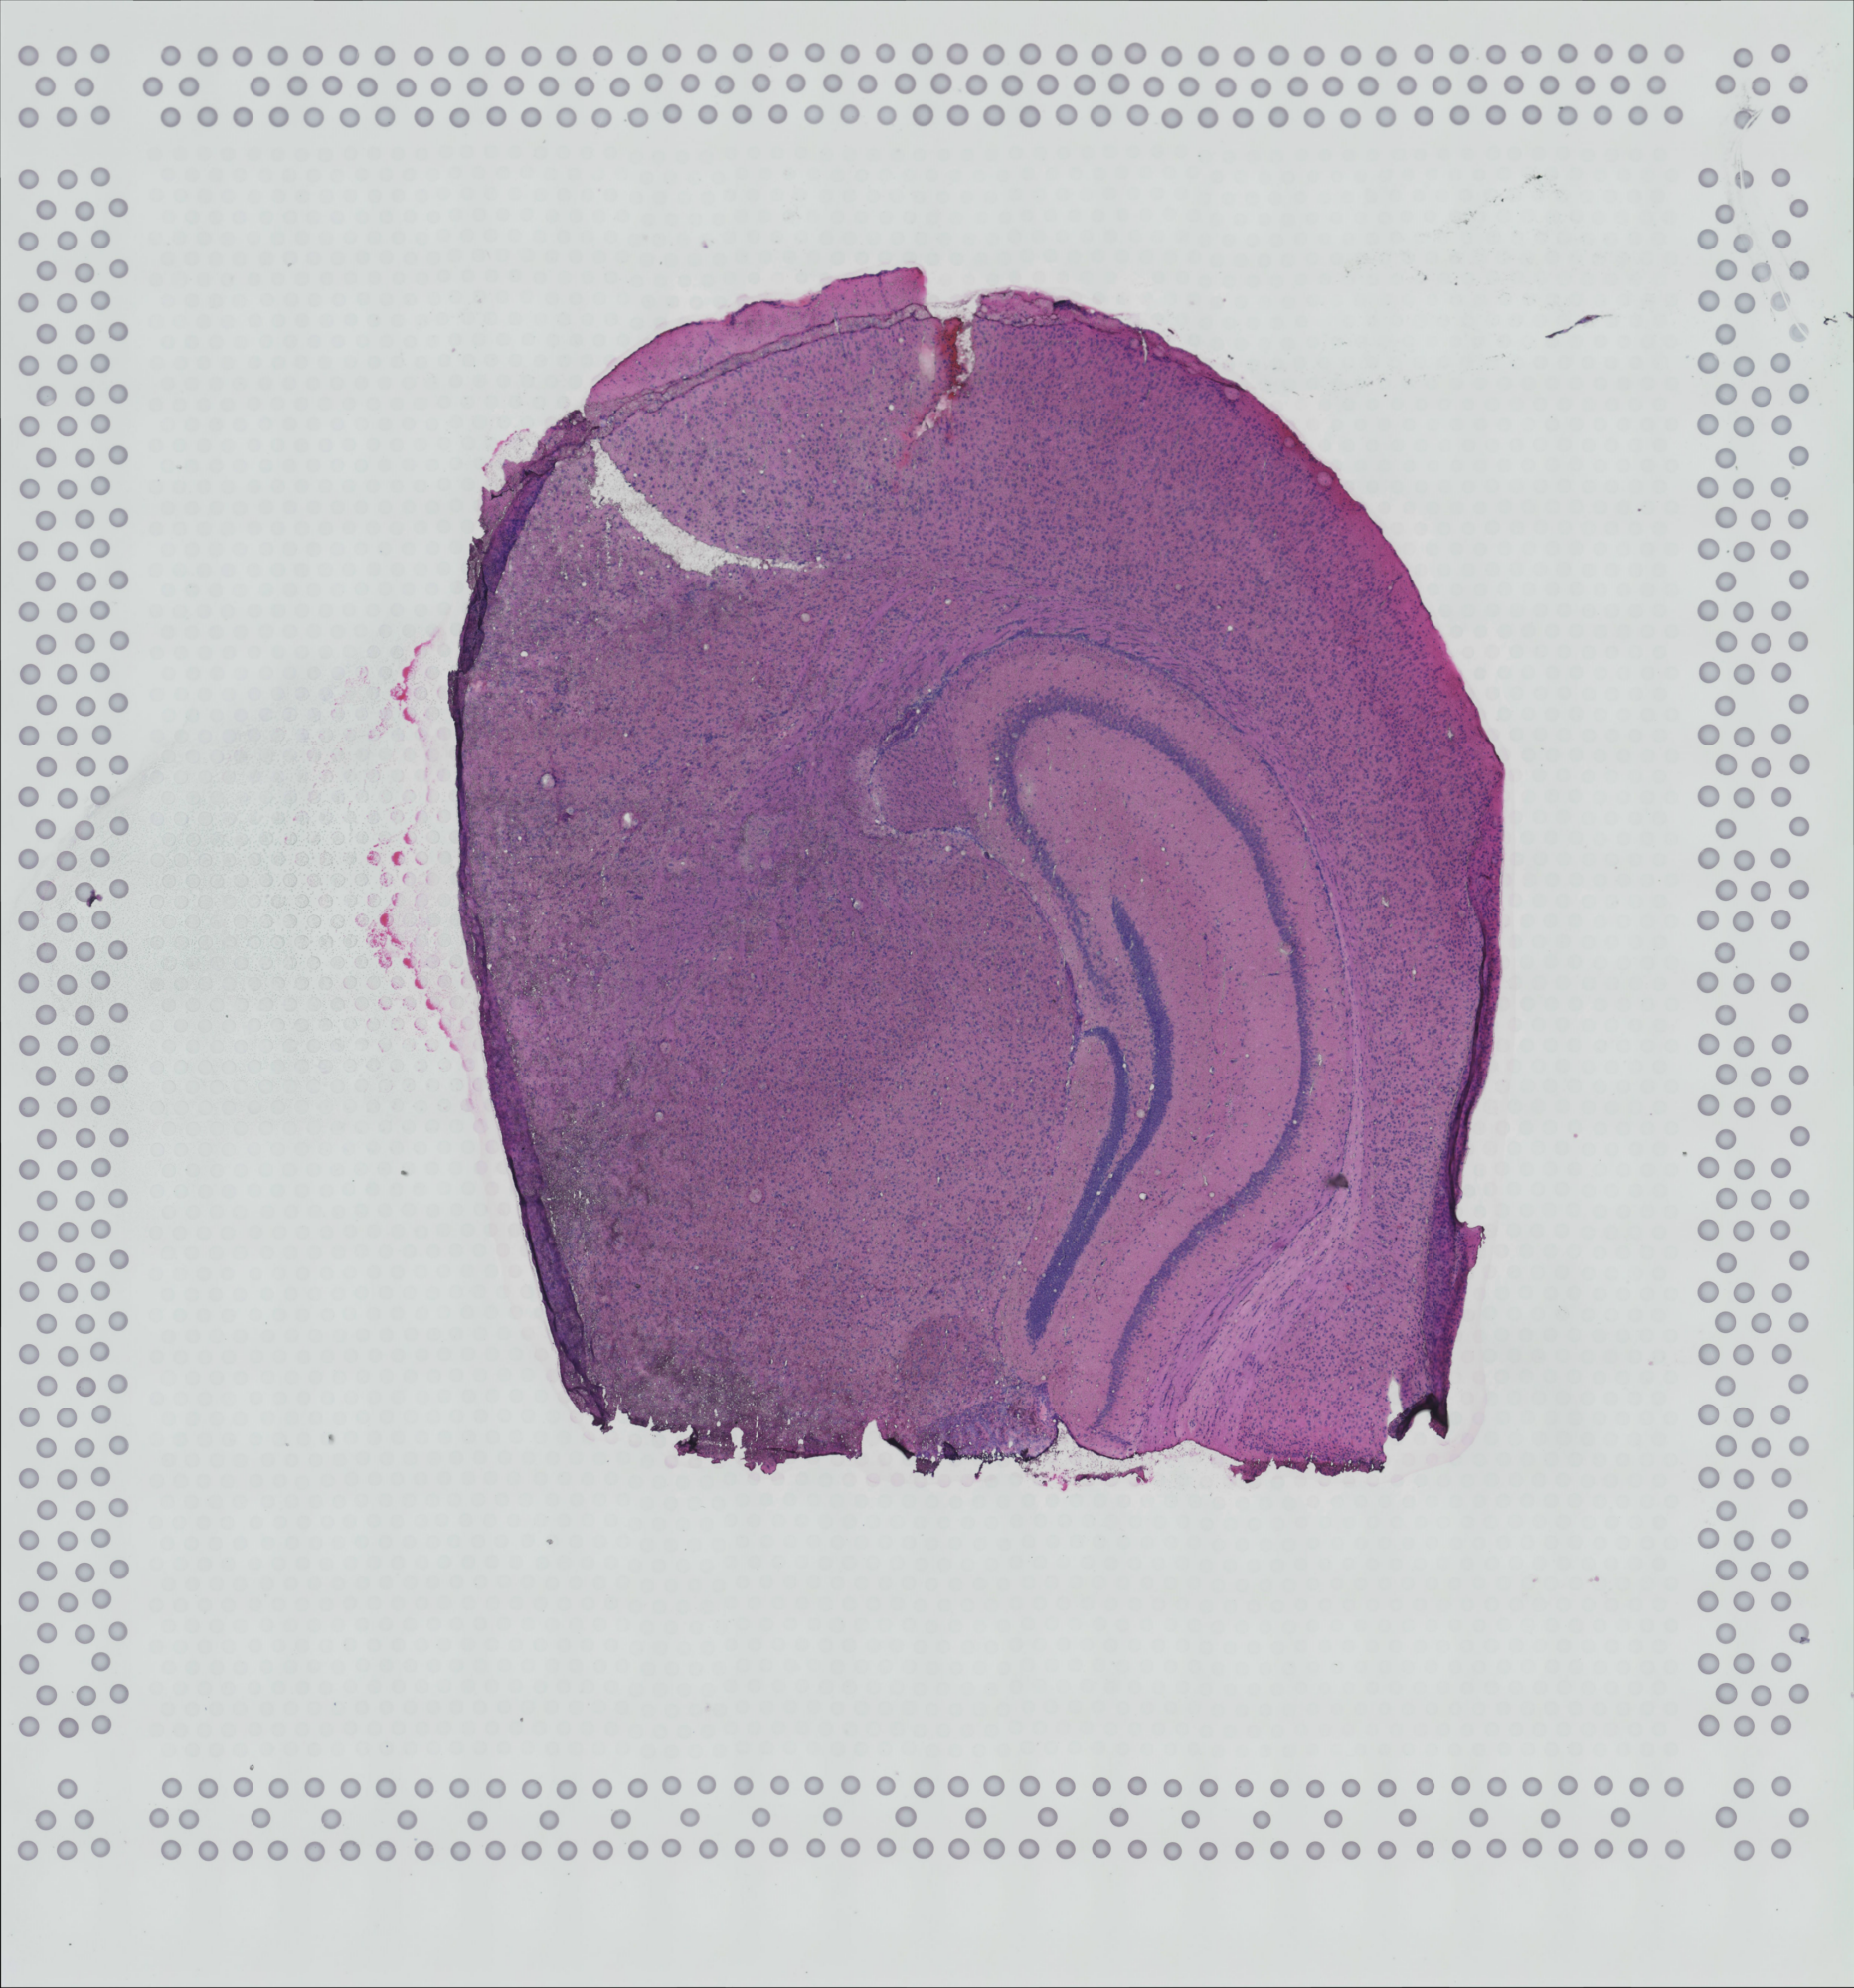

tissue_hires_image.png